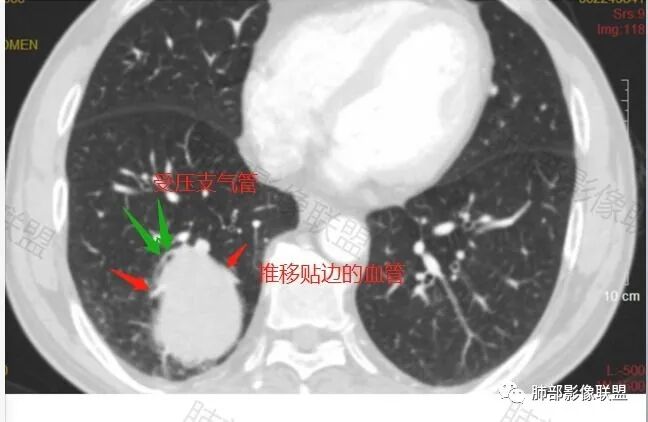

右肺下叶肿块,呈外带大内带小的椭圆形改变(内带受支气管及血管挤压原因),边缘光滑,无分叶毛刺,支气管受压,增强后,均匀延迟强化,动脉期见血管贴边,静脉期内部瘤样血管强化区,相邻胸膜无侵犯,纵隔无淋巴结肿大,符合PSP,不鉴别。

胸部CT:右肺下叶一类圆形肿块影,边界清楚,大部分边缘光滑、外缘边界模糊,邻近支气管推移、血管贴边,病灶内可见分枝状血管,平扫密度尚均匀,增强后大部分均匀延迟强化,部分与膈肌黏连、尾征?考虑:类Ca>PSP>SFT。鉴别肉瘤样Ca,CD等。

肿块位于周围(起自细支气管呼吸道上皮),均匀膨胀生长(符合良性的生长特点),病灶内部大部分密度较均匀,部分小低密度不强化区(囊变),增强强化较明显,边缘血管增粗贴边,临近支气管受压,支持PSP。

常规肿瘤如果背侧胸膜来源,肿瘤与胸膜之间不应该夹杂含气支气管,会推移

但是肺内可以将支气管外推,夹在胸膜之间

与膈面胸膜类似推断

支持肺内

但是这条血管需要交代一下:

如果这是同一根肺动脉,支持PSP

因为肺门区来源肺动脉

刷新了我的认知,这个类癌这么大一点没分叶,而且支气管血管推移那么明显。而且影像上没看到支气管截断,从病理来看,也确实没有累及支气管,

工作中肯定要鉴别类癌的,主要也是这两个鉴别,而且有时候确实比较难,但这个支气管推移情况和血管情况确实让我比较肯定是PSP,结果太笃定,错了。😂